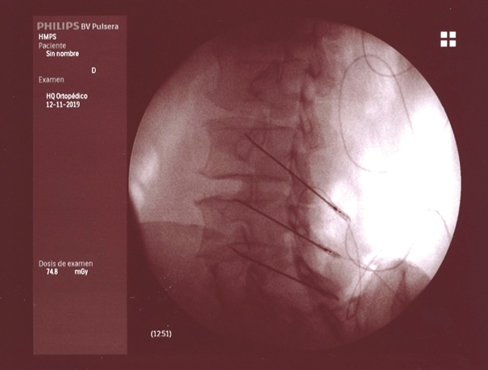

El dolor osteomuscular es la causa más frecuente de consulta en las unidades del dolor; la degeneración artrósica es la patología más prevalente dentro del dolor osteomuscular, siendo las zonas más afectadas la columna vertebral (tanto a nivel lumbar como cervical), las extremidades (rodilla, cadera, hombro), quedando el resto de las articulaciones de la anatomía como localizaciones menos frecuentes. Las técnicas intervencionistas intentan paliar el dolor causado por la artrosis, en muchos casos en pacientes con patología acompañante que hace que la posible solución quirúrgica sea descartada por su excesivo riesgo (prótesis de rodilla o cadera), o bien, como ocurre en el caso de la espondiloartrosis, el tratamiento quirúrgico no garantice la eliminación del dolor, como ocurre con la artrodesis de columna preconizada para tratar este tipo de dolor. Como siempre, la dificultad estriba en poder ofrecer al paciente un tratamiento con evidencia científica suficiente y con el riesgo más bajo posible, que conlleve a un resultado satisfactorio para él. El presente artículo pretende revisar las técnicas intervencionistas disponibles para tratar el dolor causado por la artrosis, y su grado de evidencia cuando esta está disponible.